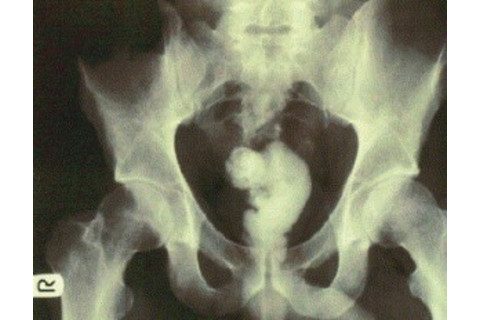

Rectal impaction with epoxy resin: A case report "We describe a unique case of a patient presenting with rectal impaction following self-administration of a liquid used as masonry adhesive for anal sexual gratification. The solidified matter required laparotomy for its removal. Strategies for removing rectal foreign bodies are discussed as well as other consequences of inserting foreign material per rectum." Bonus figure from the full text: